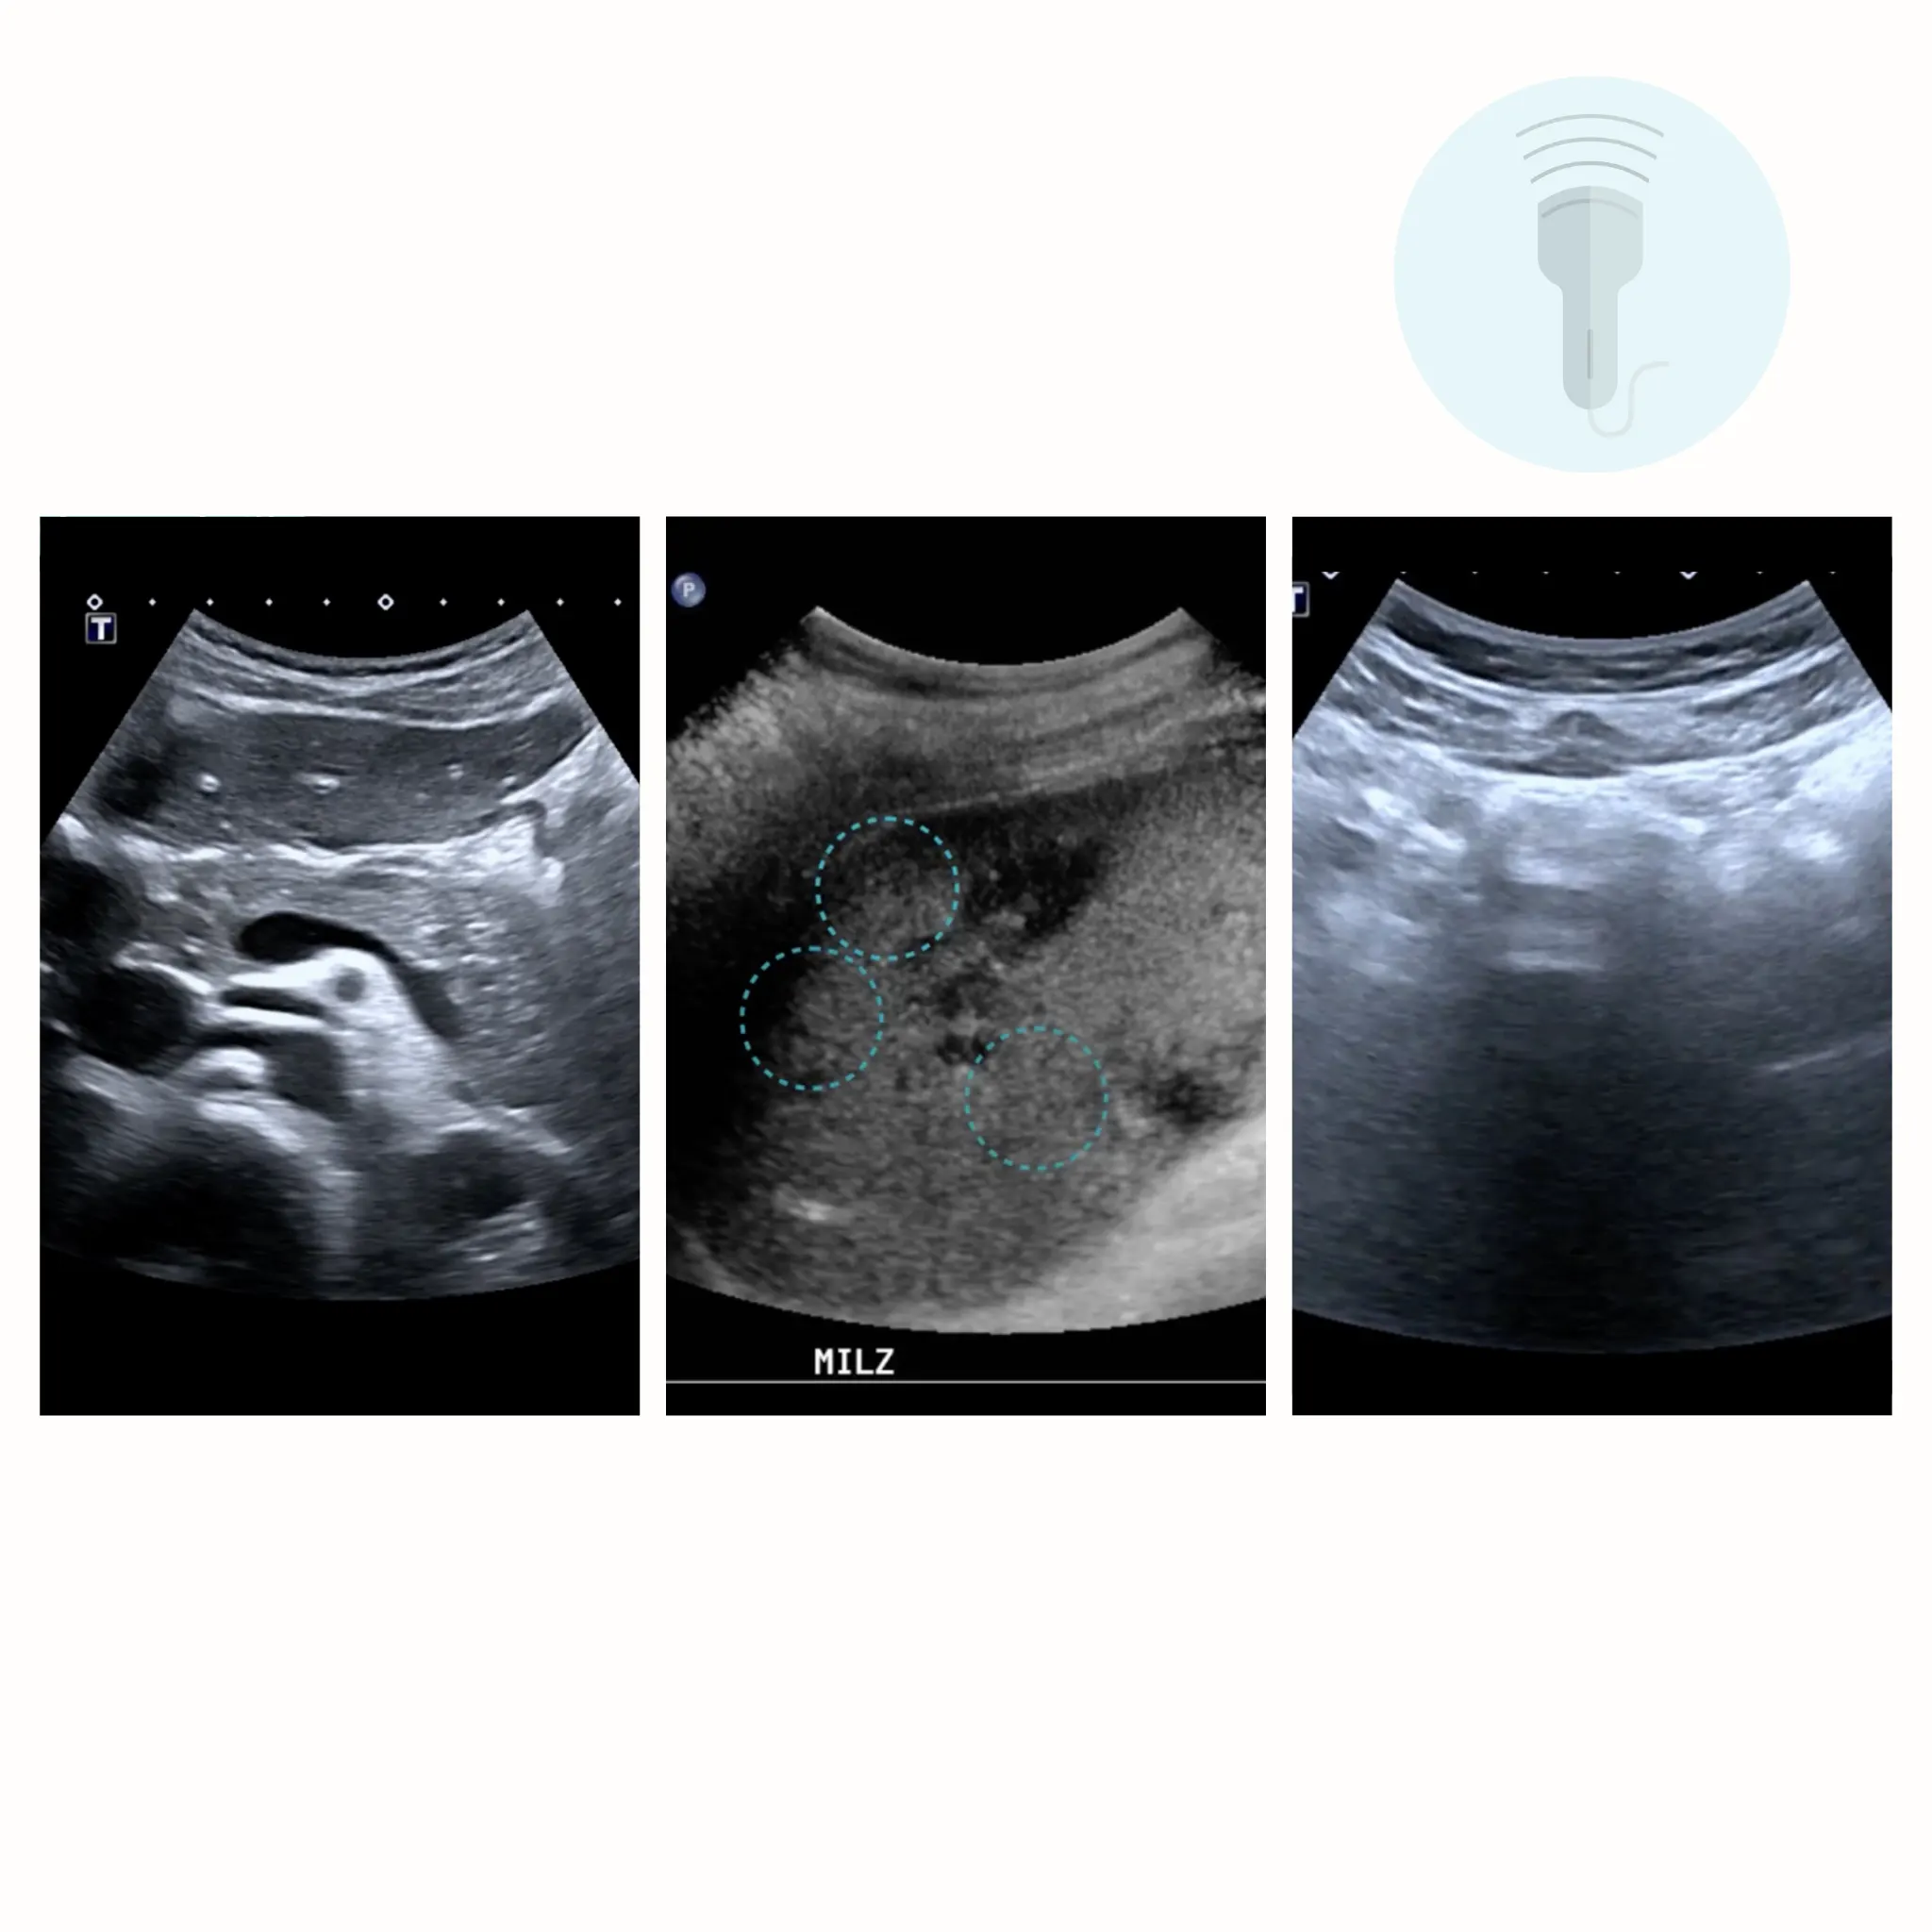

With this flexible training course, you will learn all the basics of ultrasound examinations using 14 video tutorials, numerous AMBOSS chapters and sample findings as well as multiple choice questions in a practical and multimedia format.

5) Abdomen: pancreas and spleen